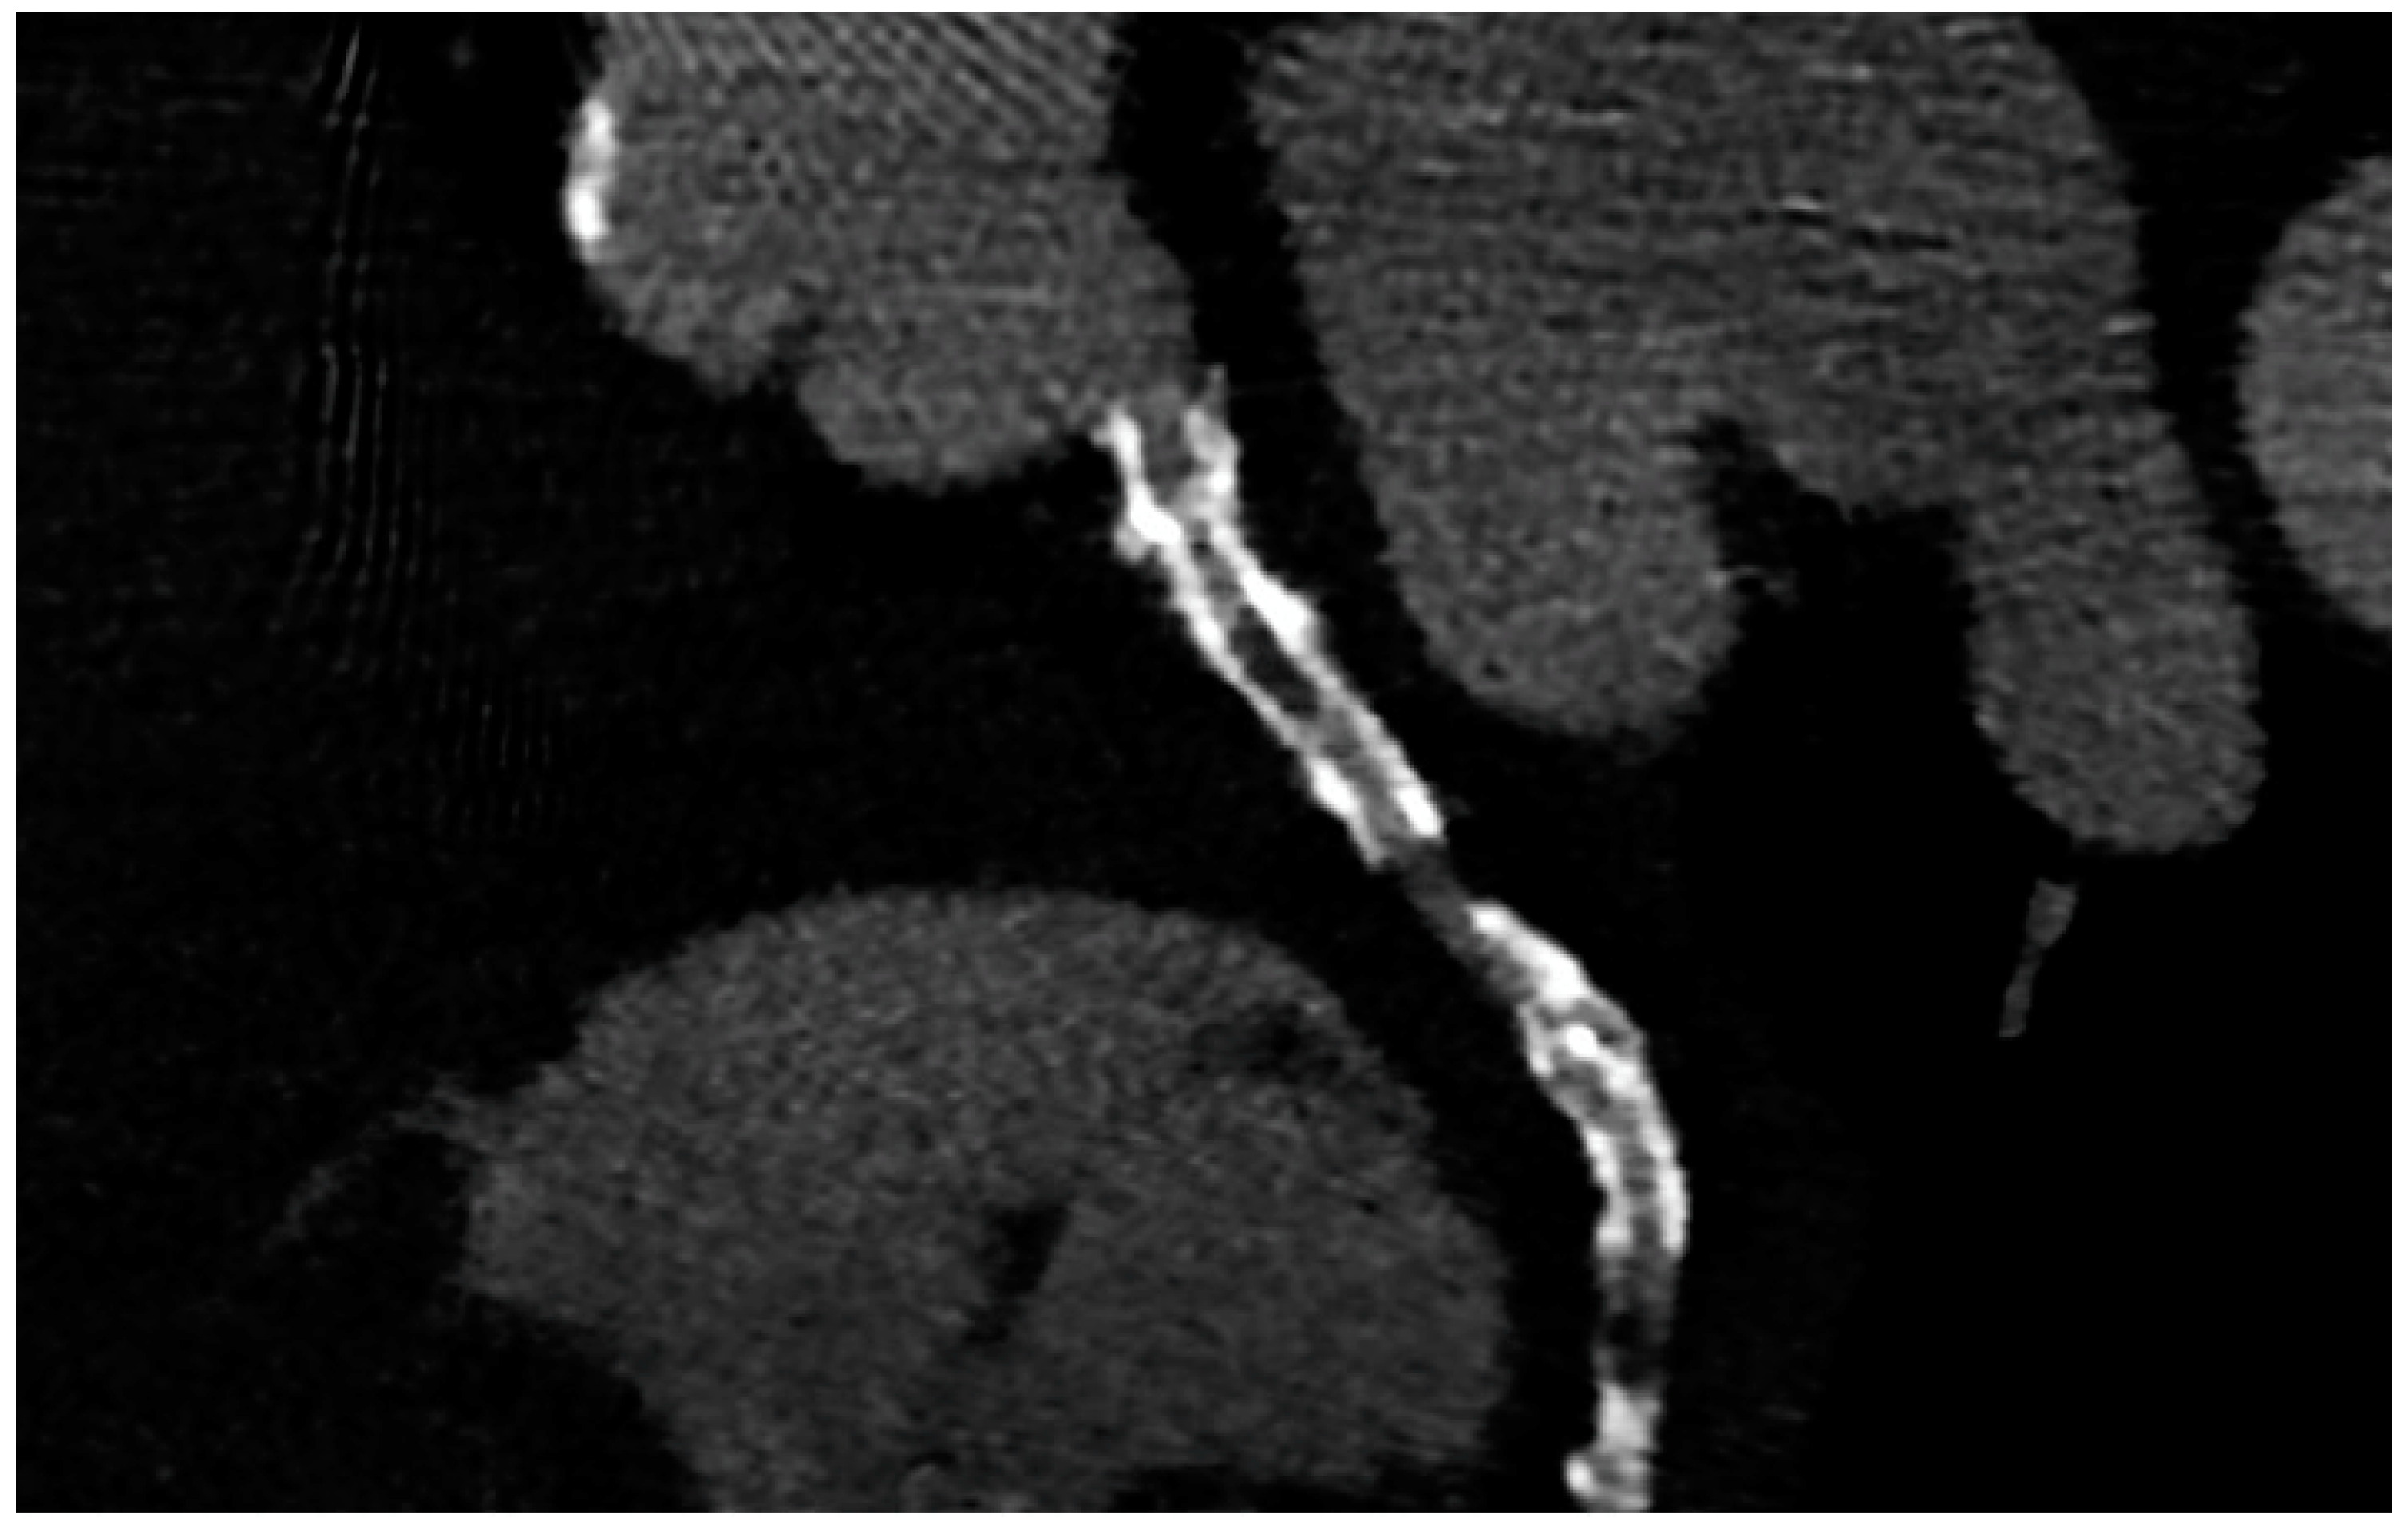

Bioresorbable scaffolds (BRS) were designed to combine the short-term advantages of permanent stents with the long-term benefit of complete reabsorption, facilitating the restoration of vasomotor and endothelial function. This technology helps prevent prolonged inflammation, maintains the integrity of distal bypass grafting sites, and allows unimpeded future vessel imaging. Despite the promising theoretical benefits of BRS, the initial generation of BRS devices exhibited higher rates of stent thrombosis in comparison to other stents [16]. Newer generation devices appear to present a viable alternative to drug-eluting stents in the management of acute coronary syndromes (ACS) for several reasons: their different composition when compared to first-generation BRS, the optimized deployment technique, and the lesion selection. Notably, ACS lesions show specific characteristics based on the pathophysiology of the disease [16]. Thus, various factors create favorable conditions for BRS implantation in ACS patients, including the vulnerable nature of the plaque, minimal calcification, the presence of a thrombus, and the relative youth of patients. BRS is radiolucent except for two metallic radio-opaque markers located at both extremities. This design feature aids in visualization during imaging procedures, ensuring accurate placement and monitoring of the scaffold. Thus, CCTA can delineate the contours of the scaffolded segment: markers easily enable the location of where BRS was implanted, and they can be distinguished from calcification because of the difference in attenuation [17]. Figure 3 shows a CCTA analysis of scaffolded coronary segments: as highlighted by orange brackets, there is evidence of two little markers of the scaffold that appear completely reabsorbed: indeed, no struts are detectable, and the vessel lumen can be analyzed in depth also in the scaffolded part with no evidence of plaque proliferation. The diagnostic accuracy of coronary CT angiography in poli-LLA (poly-L-lactide) Everolimus scaffold was studied in the ABSORB II study (A Bioresorbable Everolimus-Eluting Scaffold Versus a Metallic Everolimus-Eluting Stent II) [6]. The study provided the randomization of enrolled patients to receive treatment with BRS or drug-eluting stent. At the 3-year follow-up, patients treated with BRS underwent coronary angiography with intravascular ultrasound (IVUS) evaluation and CCTA. The study demonstrated that the CCTA diagnostic accuracy for detecting in-scaffold obstruction and luminal dimensions was similar to invasive coronary angiography (ICA) and IVUS. Analyzing scaffold segments, the sensitivity, specificity, and negative predictive values were 71%, 82%, and 97%, respectively, using IVUS as a reference. One limitation of this study was its use of a 3-year follow-up period, which did not address the crucial question of assessing the occurrence of restenosis within the initial 12 months. It is during this period that most restenosis events occur, coinciding with the presence of BRS with thicker struts in place [18]. Salinas P et al. performed the first case series of Magnesium bioresorbable scaffold investigated with CCTA at 1 year of follow-up [7]. The CCTA in-scaffold percentage diameter stenosis and area stenosis were 22% and 39%, respectively, underlying plaque growth. Additionally, performing plaque characterization, the segments treated with RMS showed that the most common component of the plaque was the fibrous one (69% of the cases), suggesting that RMS allows for the stabilization of culprit lesions [7]. Furthermore, anatomical findings can be combined with noninvasive fractional flow reserve derived from CCTA (FFR-CT) to distinguish the presence or absence of flow-limiting disease [19]. A study by Tonet E et al. investigated the performance of CCTA and FFR-CT in 26 patients treated with Magnesium bioresorbable scaffold: all patients underwent CCTA 18 months after BRS implantation. The left anterior descending artery was the most commonly affected vessel. CCTA revealed patent scaffolded segments, with complete strut reabsorption observed in 93% of cases. FFR-CT demonstrated to be feasible in scaffolded segments with a median value of 0.88 [0.81–0.91]. Figure 4 shows a case from the above-reported study: BRS (orange bracket) appears to be characterized by plaque proliferation with a prevalent calcific component. FFR-CT analysis highlighted a significant stenosis related to the plaque. In conclusion, these results suggest that CCTA plus FFR-CT is a valuable noninvasive tool for the assessment of coronary arteries in subjects treated with BRS. Scaffolded segments can be easily distinguished, allowing for quantitative measurements and the calculation of noninvasive FFR. The analysis also indicates a tendency to observe plaque stabilization in the scaffolded segments with fibrosis and calcium [8]. However, further evidence is needed in this setting of BRS patients.

Figure 3.

CCTA assessment of BRS. Orange brackets highlight the two markers of BRSs whose struts result in complete reabsorption. The vessel is also well analyzed in the scaffolded segment.

Figure 4.

Anatomical and functional assessment of ISR in a scaffold (orange bracket). ISR appears to be characterized by a major calcific part, and the stenosis results were significant under the FFR-CT assessment. FFR-CT was performed with DeepVessel FFR (DVFFR) software (Keya Medical, Seattle, WA, USA).